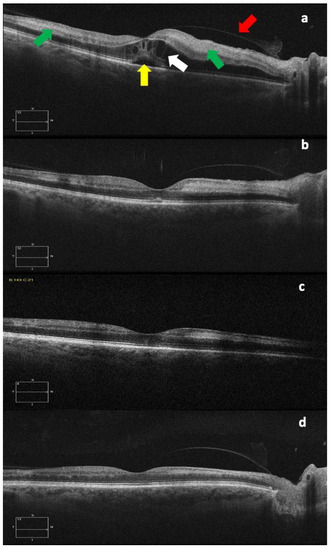

Six weeks after diagnosis, the BCVA was 20/20, with a further improvement in the color fundus photography and OCT, as can be seen in Figure 2 and Figure 3.

Figure 3. OCT images at diagnosis (a), and one week (b), three weeks (c), and six weeks (d) after diagnosis. The different images show the progressive subfoveal (yellow arrow) and intraretinal (white arrow) fluid decreasing with the gradual reduction in the retinal thickness and also the progressive reduction in the hyperreflectivity of the internal retinal layers, corresponding to the area of paracentral acute middle maculopathy (green arrows), an OCT sign that could be typical of retinal arterial occlusions. The red arrow indicates the posterior hyaloid.